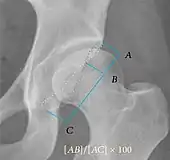

Measurements of impingement on X-ray.[notes 1][20]

MeasurementImageTargetNormal value

Alpha angle

Measured in 45° Dunn view.

Degree of bulging of the femoral head-neck junction: In normal conditions there is a symmetric concave contour at the junction of the femoral head and neck. Loss of this concavity or bone bulging may lead to cam type impingement. The degree of this deformity can be measured by the alpha angle. Although it can be measured in the cross-lateral view, the 45° Dunn view is considered more sensitive and the frog leg view more specific in determining pathologic values.

• Normal: ≤68° in men, ≤50° in women

• Borderline: 69° to 82° in men, 51° to 56° in women

• Pathological: ≥83° in men and ≥57° in women

Femoral head-neck offset

Measured in cross-lateral view.

Offset of the femoral head with regard to most prominent aspect of the femora neck>10 mm

Offset percentage Femoral head-neck offset related to femoral head diameter >0.18

• less indicates high risk of cam type impingement